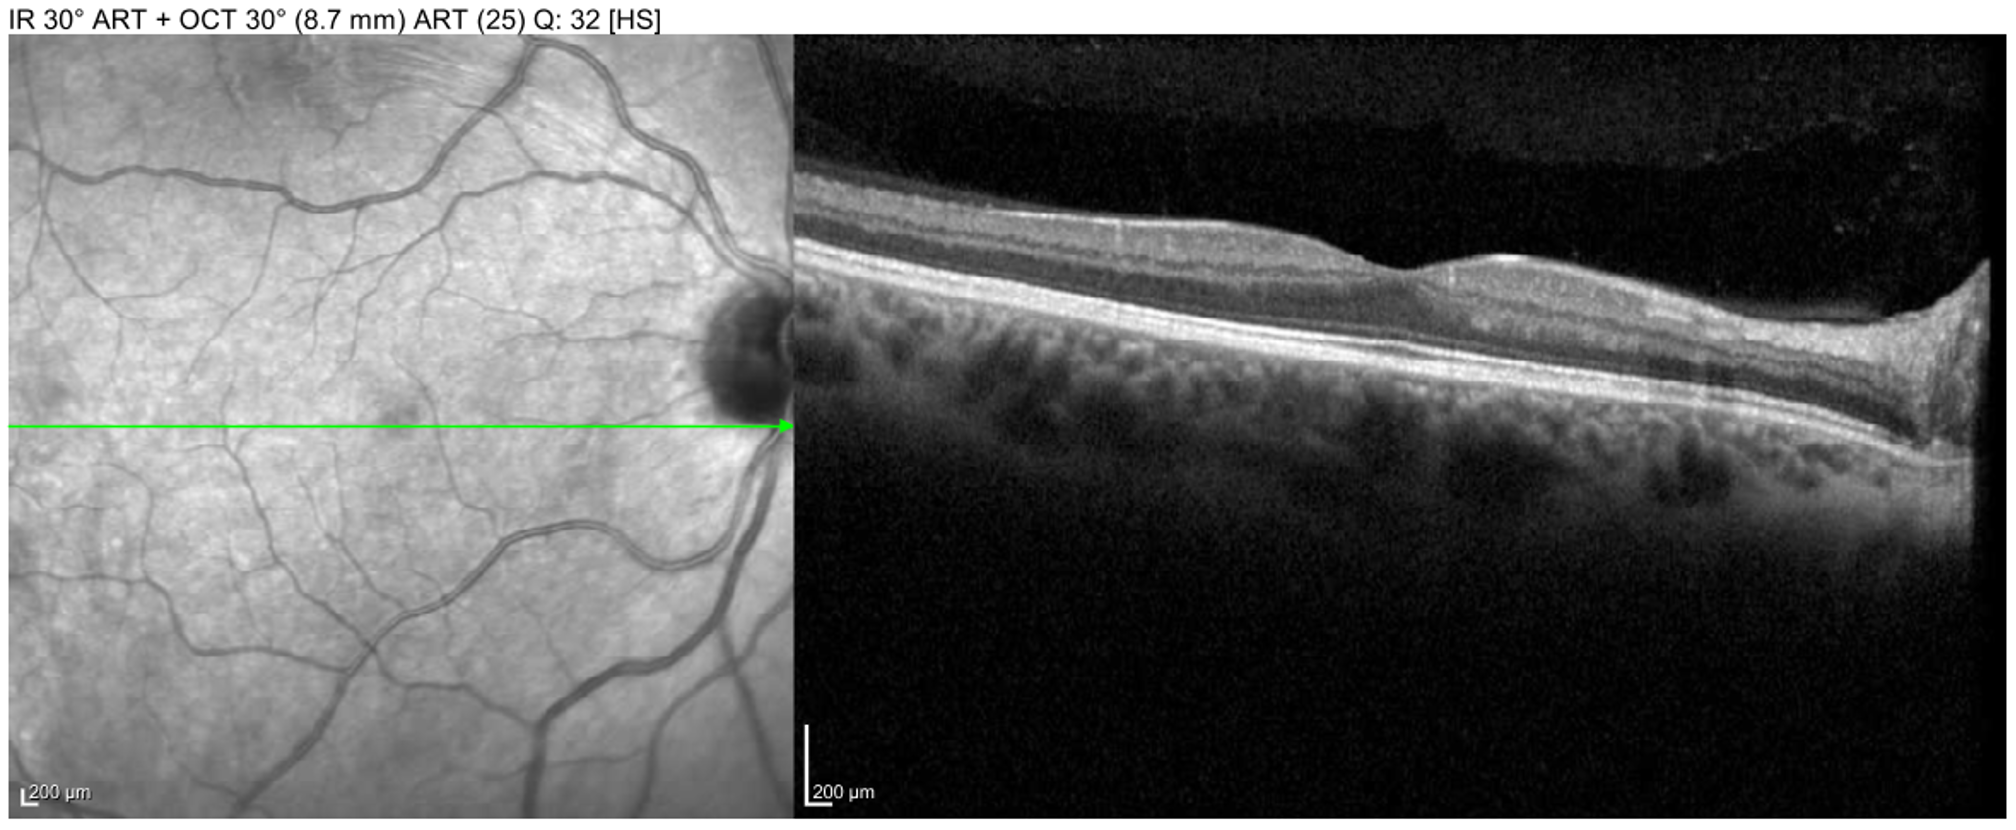

• OCT Macula (Figures 5 and 6):

• OD: one superior area of BRAO visible on near infrared

• OS: large superior BRAO involving the macula

Macula OCT of the left eye showing large BRAO in the macula with inner-retinal edema and hyperreflectivity.

Enlarge Download

Figure 6. Macula OCT of the left eye showing large BRAO in the macula with inner-retinal edema and hyperreflectivity.